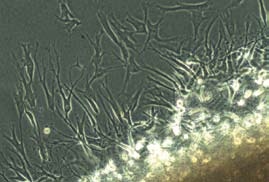

A o co vlastně jde? Pacientovi se odebere malá část chrupavky (2 x 3 mm), ze které se v superčistých prostorách laboratoří NTC a. s. vyizolují buňky pacienta zodpovědné za tvorbu chrupavky (chondrocyty). Buňky jsou následně tři až čtyři týdny kultivovány v laboratoři NTC a. s., než je dosaženo jejich potřebného počtu. Pak jsou smíchány s tkáňovým lepidlem a je vytvarován požadovaný tvar nové chrupavky. Nová chrupavka je přepravena do nemocnice, kde ji lékař pomocí tkáňového lepidla implantuje pacientovi do místa defektu. „Defekt chrupavky se vyplní vlastními buňkami pacienta, což je zásadní výhodou oproti jiným metodám, které jsou technicky náročné a způsobují vysoké zatížení pacienta, jako například implantace autologních osteochondrálních štěpů (mozaiková plastika). Naopak využití vlastních buněk je nejlevnější metodou léčby a zároveň se při těchto postupech zvyšuje kvalita života. Zatím dosahujeme špičkových klinických výsledků a za celé období aplikace nebyly hlášeny ani zjištěny žádné nežádoucí účinky, pooperační komplikace nebo selhání implantátu," dodává MUDr. Kubešová.

2. fáze - Výroba nové chrupavky

Jakmile je chrupavková tkáň odebrána, je převezena do laboratoří NTC, kde se následně zpracovává v tzv. „superčistých prostorách". Z tkáně jsou získány chrupavkové buňky, které jsou dále množeny až do požadovaného počtu. Doba, za kterou jsou buňky namnoženy, je individuální, dle růstu buněk (i chrupavkové buňky rostou každé jinak rychle). Pro nárůst dostatečného počtu buněk je třeba doba přibližně 3-4 týdnů. Poté, co je dosaženo vhodného počtu buněk (záleží na velikosti připravovaného chondrograftu), jsou buňky smíchány s takzvaným tkáňovým lepidlem, aby vznikla nová chrupavka, která vyplní chybějící nebo poškozenou část chrupavky. Velikost připravované chrupavky je dána velikostí poškozené chrupavky, kterou lékař zadá již na počátku kultivace buněk.